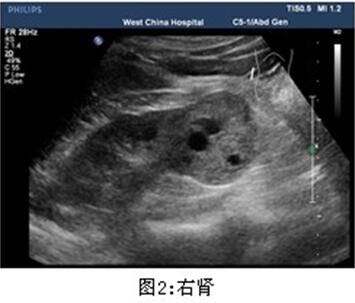

查体无特殊。 辅助检查: 泌尿系彩超示:右肾下极稍高回声团,大小约4.7*4.4cm,边界尚清,内回声不均质。

患者泌尿系彩超发现右肾下极稍高回声团,大小超过4cm,考虑肾错构瘤可能,手术切除指证明确,遂行腹腔镜右肾部分切除术。